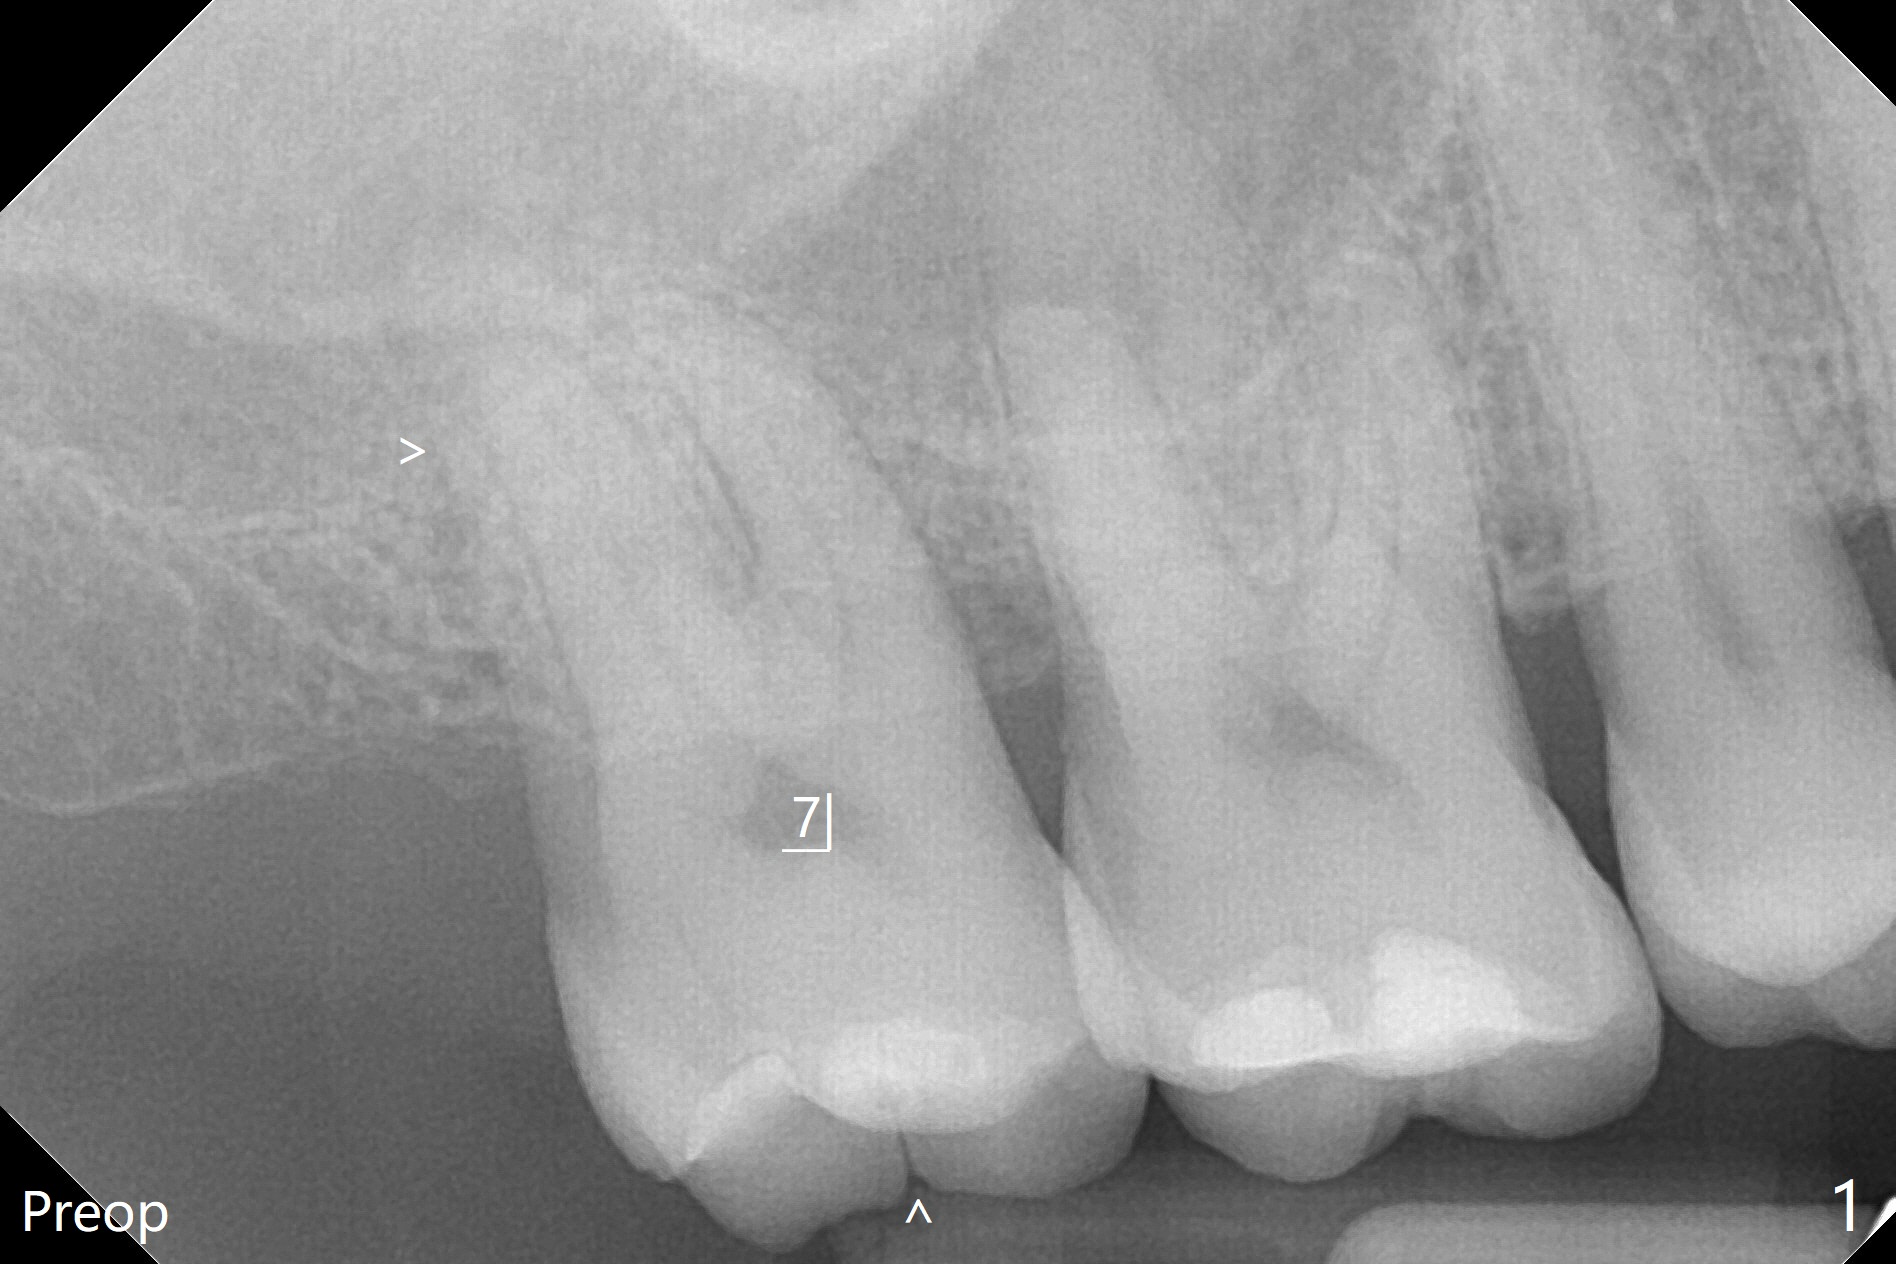

在导航协助下,我们可以一期准确进行上颌窦提升,即刻种植,即刻修复。56岁男(吸烟)右侧上颌窦有粘液囊肿,右上七牙齿折裂(图一(术前):^),CT检查表明植体植入腭侧牙槽窝比较合适(图一:>)。为了减少对囊肿损伤,我们使用导板(图二 *)完成初步钻洞,接近上颌窦底板,然后放置粘性骨(>),用4x10毫米dummy(报废)植体慢速(15 RPM)旋入进行内提升,同时准确控制深度。再次放置骨粉,使用4.5x10毫米报废植体上推;最后放置骨粉后(图三 >),植入正式植体(5x9毫米,扭力大于35Ncm)和修复基台(6.5x4(4)),怀疑后者没有完全就位,后来使用小的基台(图四,并且调整高度),植体和基台周围放置骨粉(*),然后安置临时牙冠。咬颌面没有接触,临时牙冠主要目的是防止骨粉丢失。反复告诉病人不能咬东西。术后两周病人主诉临时牙冠太大,试图减少颊舌侧向,不幸的是却减少近中远中向,造成临时牙冠不稳定。一周后牙冠和基台松动,取出,放置愈合螺帽,牙槽窝基本愈合。病人将术后近四个月复诊,拍摄根尖片和咬翼片,如果骨质愈合良好,尝试在尚未完全愈合的伤口放置小号愈合基台。术后5个月牙冠粘固后拧紧植体松动,取出(图五(*:缺损)),植骨。四个月后骨质高度近5毫米(图六)。再次植入尽量避免窦膜穿孔(粘液囊肿),塞入PRF膜。Return to Upper Molar Immediate Implant, Prevent Molar Periimplantitis (Protocols, Table) No Deviation 不理想病例 开场白Xin Wei, DDS, PhD, MS 1st edition 08/10/2020, last revision 06/12/2021